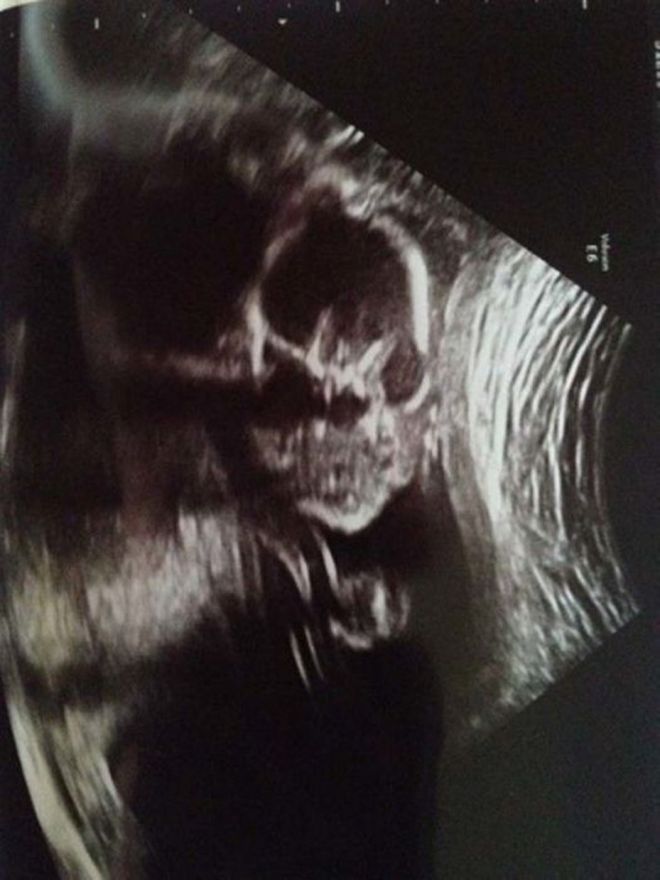

Հմմ, սա իսկապե՞ս փոքրիկ երեխա է։